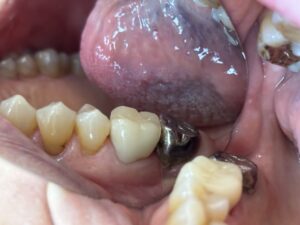

金属アレルギーの原因になる得る、銀歯を白くしたいという患者さんがいますが、保険適応でCADCAMやハイブリッドセラミックで治療してくれる歯科医院が、相変わらず少ないと言う患者様が来院されますね。

違いや比較としては 保険のは年数が経過すると 劣化したり変色する 欠けたり割れたりする可能性があります。

保険はプラークが付きやすいことがあるので歯周病の患者様、歯茎が腫れっぽい、歯肉炎になりやすい方、歯石が多く歯周病の方にはよく歯磨きするようにアドバイスしております。